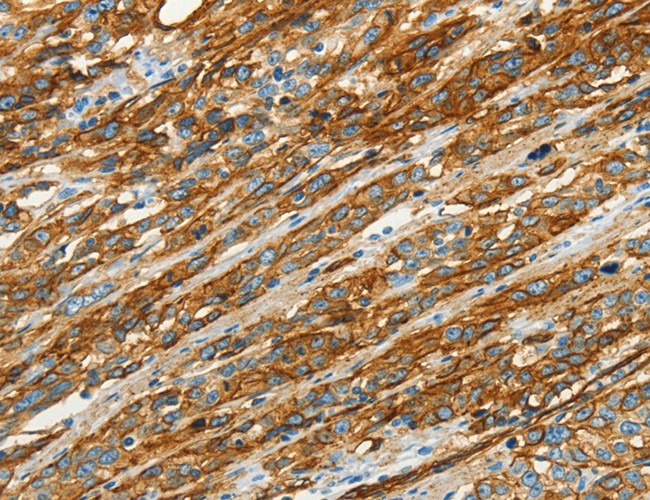

IHC (Immunohiostchemistry)

(Immunohistochemistry of paraffin-embedded Human esophagus cancer using CAV1 Polyclonal Antibody at dilution of 1:40)